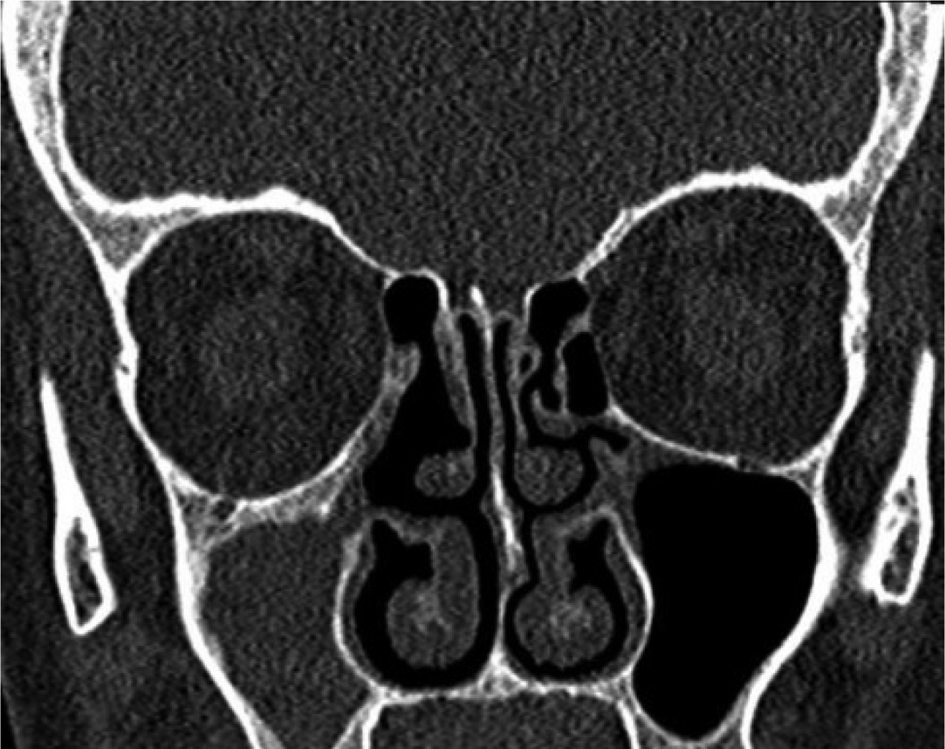

General symptoms of sinusitis were present in 21 patients and absent in 33 patients. Eleven patients had grade I (Figure 1), 35 patients had grade II (Figure 2) and 8 patients had grade III (Figure 3) chronic maxillary atelectasis. Seven patients met the silent sinus syndrome criteria; one patient with chronic maxillary atelectasis grade III was symptomatic and therefore not considered to have silent sinus syndrome. Table 2 reports the clinical features.

Fig. 1. Coronal computed tomography scan of the paranasal sinus demonstrating lateralisation of the right uncinate processes (grade I chronic maxillary atelectasis).